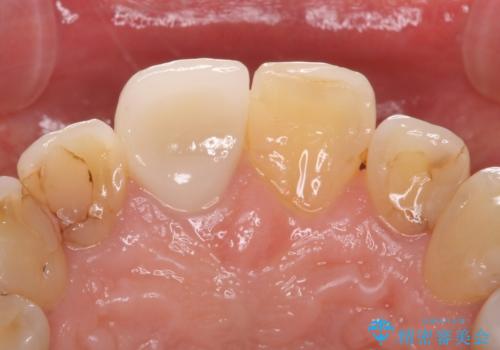

- 継ぎ接ぎになった前歯を綺麗にしたいとのことで来院されました。

継ぎ目のないクラウンで修復処置していきます。

- 左上2 仮歯+ジルコニアクラウン:11,000円+121,000円費用は治療当時の料金となります